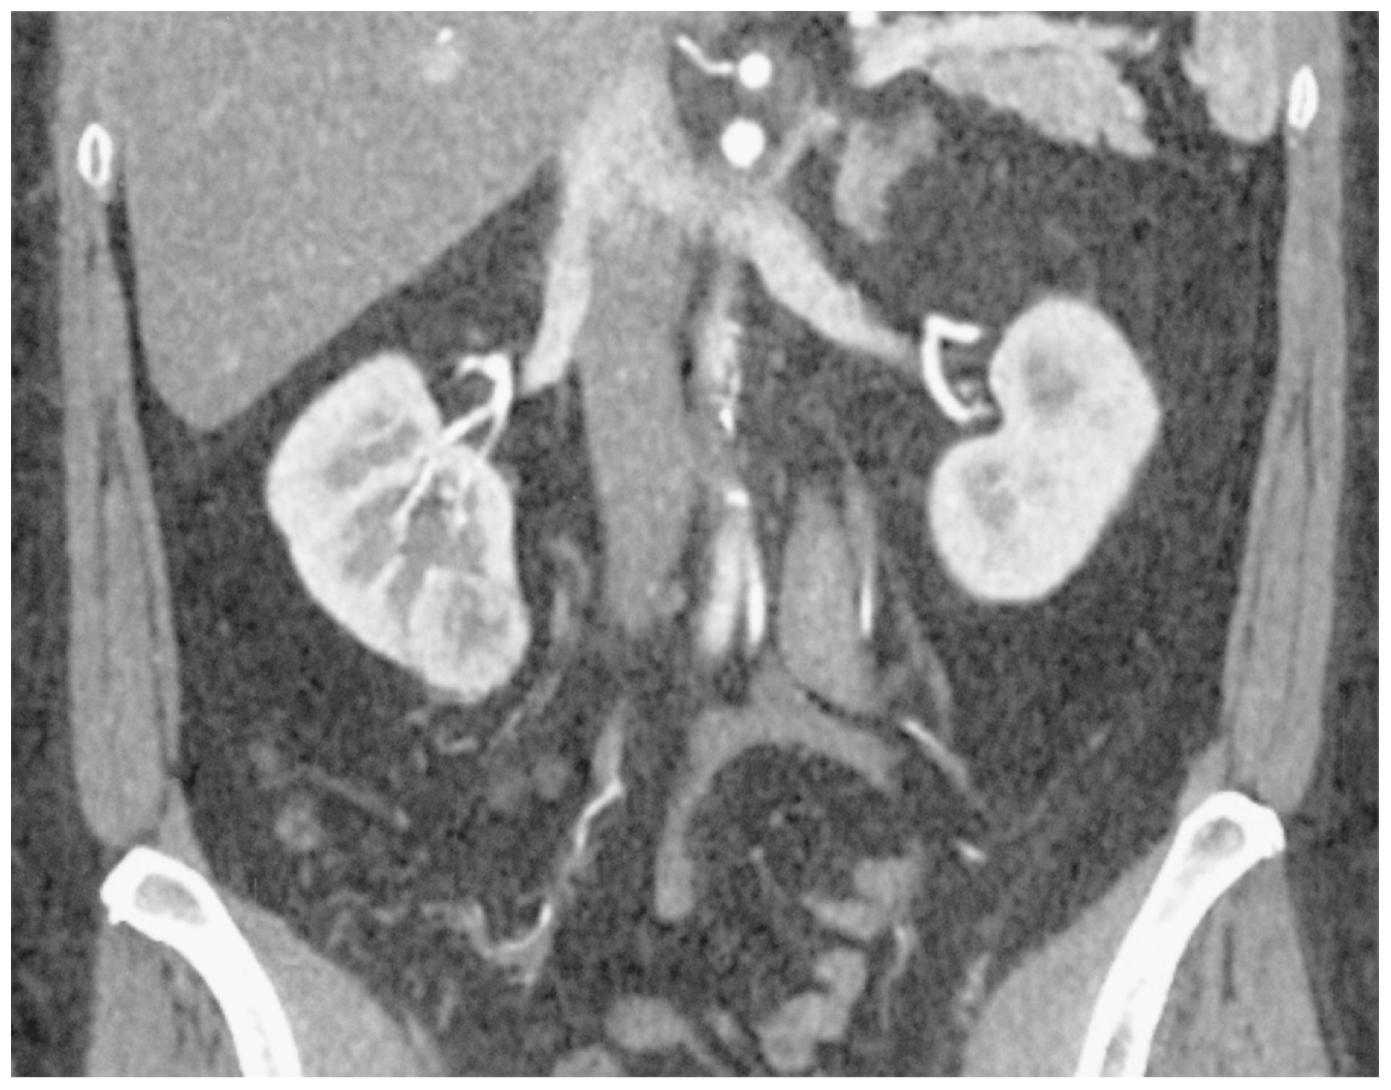

60歳の男性。3週間前に受けた人間ドックの腹部超音波検査で右腎下極に径2.5cmの腫瘤を指摘されたため来院した。自覚症状はない。尿所見:蛋白(-),糖(-),潜血(-),沈渣に赤血球,白血球を認めない。血液所見:赤血球474万,Hb 14.9g/dL,Ht 43%,白血球5,900,血小板20万。血液生化学所見:総蛋白7.1g/dL,アルブミン4.1g/dL,総ビリルビン0.9mg/dL,AST 24U/L,ALT 26U/L,LD 156U/L(基準124~222),尿素窒素14mg/dL,クレアチニン1.0mg/dL,Na 138mEq/L,K 4.3mEq/L,Cl 102mEq/L。CRP 0.1mg/dL。腹部造影CTの冠状断像を下に示す。胸腹部CTでは転移を認めない。